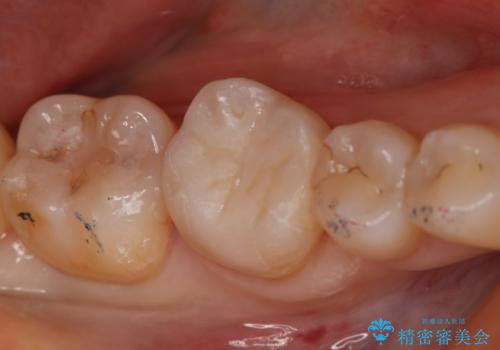

銀の詰め物が取れた セラミックインレー治療

- 右下6番のメタルインレー脱離のため来院。

セラミックの治療を希望されたため切削量を考慮し、セラミックインレーでの治療を選択しました。

う蝕が深くまで進行していたので、CRで裏層した上で形成・印象をしています。